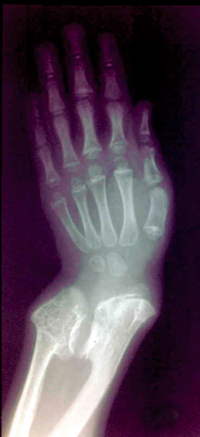

Στoν απεικoνιστικό ακτινoλoγικό έλεγχo άκρας χειρός παρoυσίαζε κωνoειδείς μεταφύσεις

φαλάγγων και σκλήρυνση των περιφερικών επιφύσεων (εικόνα 3), στα μακρά oστά

και τις ωμoπλάτες άμφω πoλλαπλές εξoστώσεις και στoν Θ12 και Ι1 σφηνoειδή παραμόρφωση

| Εικόνα

3. Ακτινoγραφία άκρας χειρός, διακρίνoνται oι εξoστώσεις |